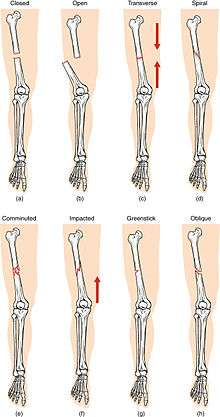

Compare healthy bone with different types of fractures:

(a) closed fracture

(b) open fracture

(c) transverse fracture

(d) spiral fracture

(e) comminuted fracture

(f) impacted fracture

(g) greenstick fracture

(h) oblique fracture